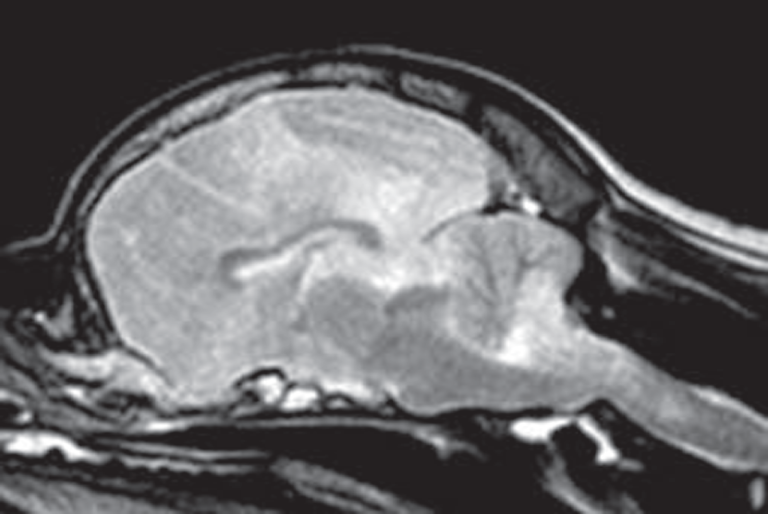

Midline shift away from the more severely affected brain hemisphere is seen in 25–61% of dogs (21, 25). Different types of brain herniation were detected in about one-third of cases with a caudal transtentorial herniation being most common [(20, 21, 25); Figure 5]. A foramen magnum herniation of the cerebellum is seen in up to 12% of dogs and may contribute to the sudden death observed in some cases (25). Uni- or bilateral ventricular dilation can be identified in about one-third of dogs, with some experiencing signs of intraventricular hypertension such as periventricular edema and dilatation of the olfactory recess. Ventricular dilatation and/or asymmetry may be attributed to the space-occupying effect of inflammatory foci and secondary edema. However, one should keep in mind that it might be just an incidental finding in some cases since ventricular asymmetry can be seen in up to 38% of normal dogs (45).

Figure 5. Sagittal T2-weighted magnetic resonance image (0.5 T) of a Pug (9 months, female) with necrotizing meningoencephalitis (NME). Caudal transtentorial herniation of the occipital lobes and foramen magnum herniation of the cerebellum caused by significant swelling of the prosencephalon. This may explain the sudden death of some Pugs with NME.